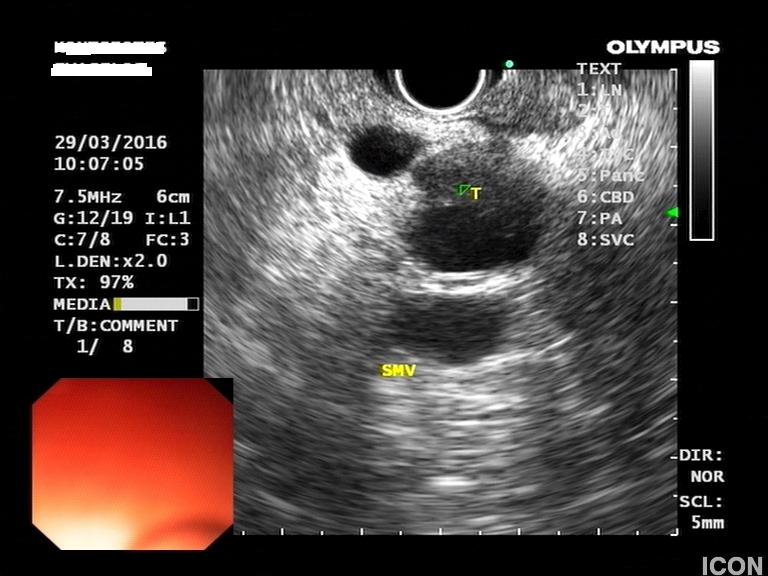

Ο ασθενής υποβλήθηκε σε ενδοσκοπικό υπέρηχο που έδειξε μια υποηχοϊκή μάζα διαμέτρου 21 χιλιοστών, με σαφή όρια, στην παγκρεατική κεφαλή και μεγάλη διάταση του χοληδόχου πόρου και του παγκρεατικού πόρου (διάμετρος 12 χιλιοστά).

Η μάζα είχε ξεκάθαρο διαχωριστικό όριο λίπους από την άνω μεσεντέριο φλέβα και δεν διηθούσε κανένα άλλο μεγάλο αγγείο της περιοχής (πυλαία φλέβα, σπληνοπυλαία συμβολή και αρτηρίες). Έγινε βιοψία με λεπτή βελόνη (FNA Χ3) και το κυτταρολογικό υλικό ήταν θετικό για αδενοκαρκίνωμα παγκρέατος. Το νεόπλασμα κρίθηκε χειρουργήσιμο και ο ασθενής υποβλήθηκε σε επέμβαση Whipple κατά την οποία αφαιρέθηκε πλήρως η παγκρεατική κεφαλή και ο όγκος σε υγιή όρια αλλά και 12 λεμφαδένες που ήταν όλοι αρνητικοί για κακοήθεια. Ο ασθενής υποβάλλεται σε συμπληρωματική χημειοθεραπεία.

Μάζα σώματος παγκρέατος στον ενδοσκοπικό υπέρηχο

Διαχωριστικό όριο μεταξύ μάζας και αγγείου